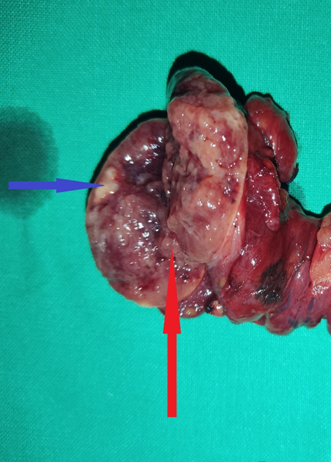

Appearance of parathyroid adenoma , after opening of the carotid sheath (Courtesy Dr. V. Penopoulos)

Blue arrow — Parathyroid adenoma. Green arrow — Area of necrosis and hemorrhage (Courtesy Dr. V. Penopoulos)